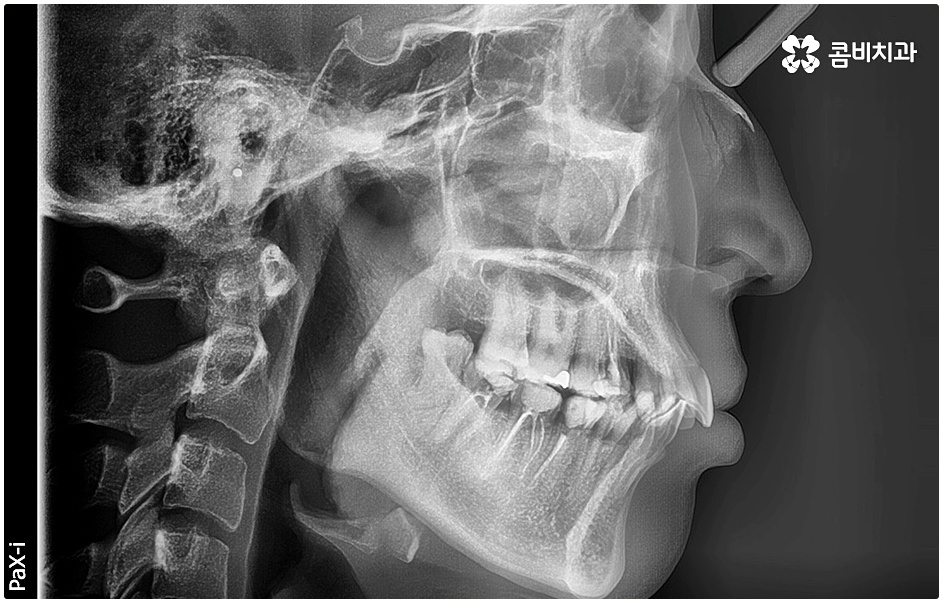

특히 돌출입, 주걱턱 등 부정 교합 요소를 발견했다면 교정이 가능한 시기에 바로 시작하는 게 좋은데 치과에서는 보통 초등학교 고학년부터 중학교 저학년 사이에 교정 치료를 시작하도록 권유하는 편이며 개인마다 치아 발육 속도에 차이가 있으므로 만 7세 정도부터 정기적인 검진을 통해 성장 추이를 지켜보면서 각자 다른 상태에 맞게 교정 치료를 진행하고 있는데요.

돌출입, 주걱턱 등은 얼굴 골격 구조, 치열과 관련된 부분이기 때문에 얼굴뼈가 느슨하게 연결돼 있고 성장판이 아직 닫히지 않은 소아기에 보다 쉽게 돌출치아교정 이 가능하니 이에 대해서도 잘 고려해 보시길 바라고 있습니다.

돌출입에는 두 가지 경우가 있는데 먼저 치아들의 각도가 앞으로 뻗어서 돌출되는 경우와 골격 구조상 튀어나온 경우 (즉, 치아를 잡아주는 상악 치조골, 잇몸 자체가 돌출된 경우 또는 하악 턱이 뒤로 후퇴한 경우) 이렇게 나눌 수 있으며 정확한 원인을 파악하는 것이 중요하기 때문에 꼼꼼한 검진 및 면밀한 상담이 우선시 될 필요가 있어요.

치료를 위해서는 입을 안쪽으로 넣기 위한 공간을 확보해야 하므로 보통 위아래 소구치 총 4개의 치아를 발치하여 그 공간을 활용해 튀어나온 치아와 잇몸을 전체적으로 뒤로 이동시키는 방법을 사용하나 최근에는 미니스크류, 치간 삭제 등의 방법을 이용하여 비발치 교정을 진행하기도 하니 먼저 자신의 상황을 꼼꼼하게 살펴보고 부정 교합의 원인과 정도부터 정확하게 파악하는 것이 필요한 거에요.